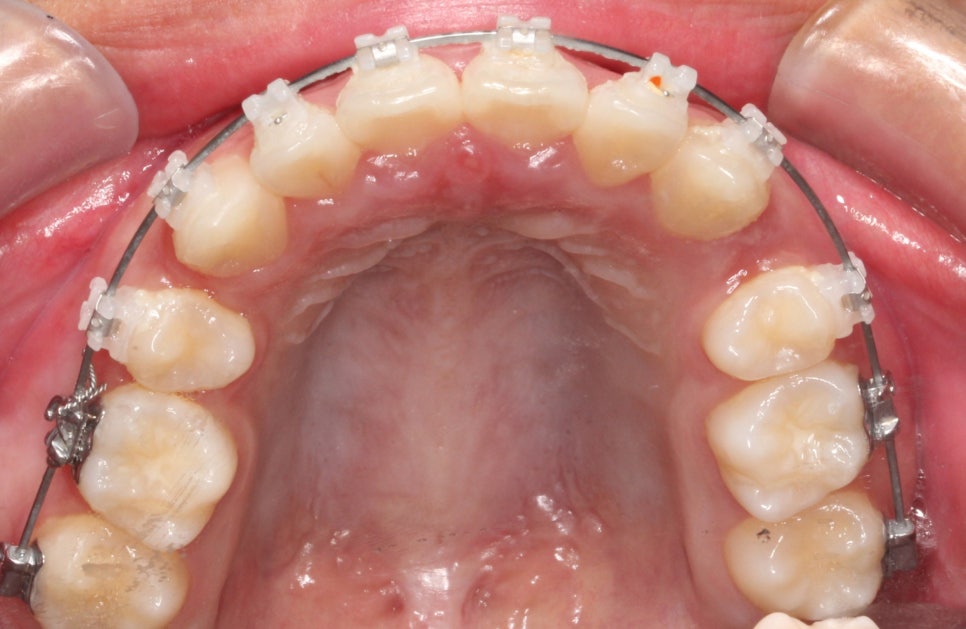

또한 위아래 덧니가 심했어요.

특히 위쪽 어금니쪽은 치료가 쉽진 않았습니다.

위쪽 2개 치아의 발치 후 교정치료를 진행했습니다.

위쪽은 발치를 해야하기 때문에, 그리고 어금의 개선이 오래걸리기 때문에 아래쪽 장치를 거의 6개월이 지나서 붙이게 되었습니다.